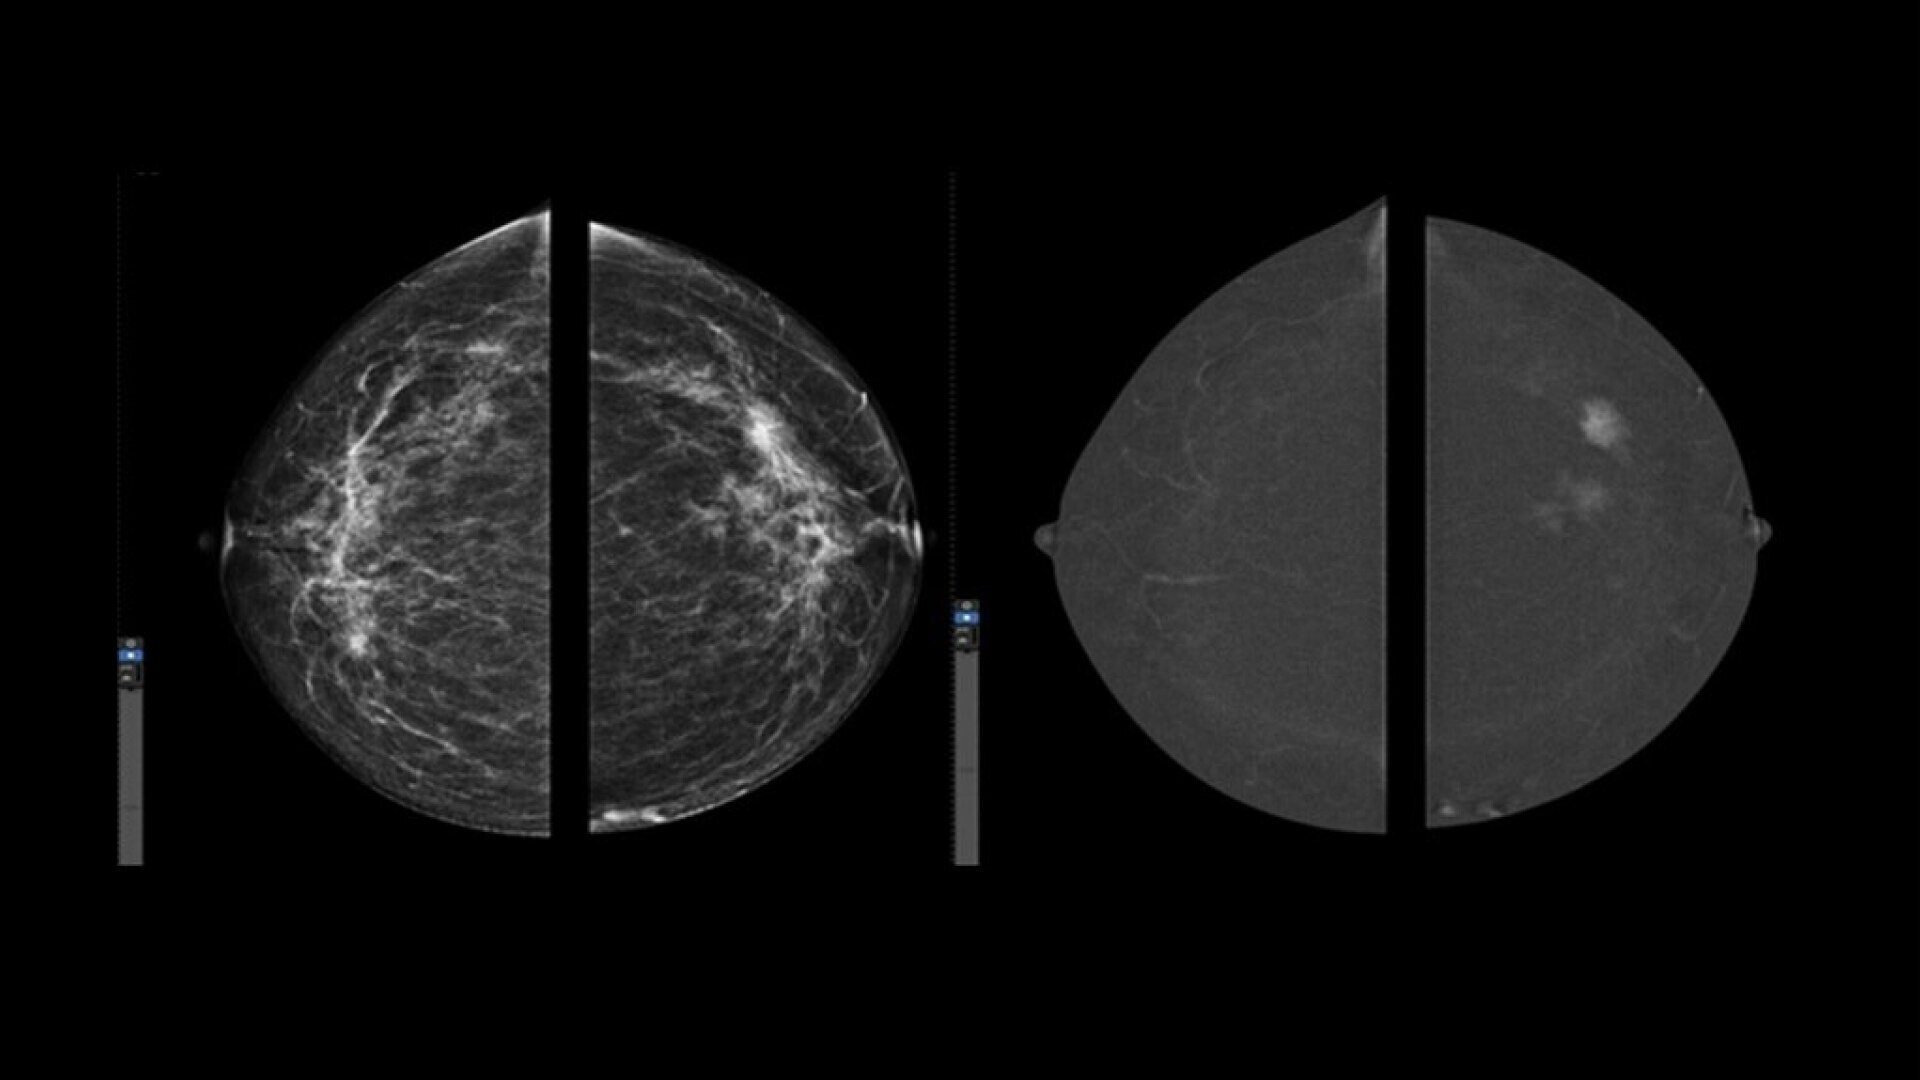

Exceptional performance

Improve clinical accuracy

• Find lesions that cannot be seen on routine mammography6,7,8.

• Provide high specificity for low false-positives1.

• With Nira, overall Image quality was better assessed in more than 98% of the images presented by all the readers9.